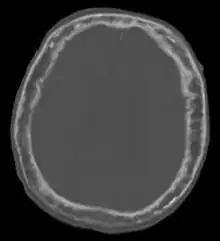

| "This 92 year-old male patient presented for assessment of sudden inability to move half his body. An incidental finding was marked thickening of the calvarium. The diploic space is widened and there are ill-defined sclerotic and lucent areas throughout. The cortex is thickened and irregular. The findings probably correspond to the 'cotton wool spots' seen on plain films in the later stages of Paget’s disease." | |